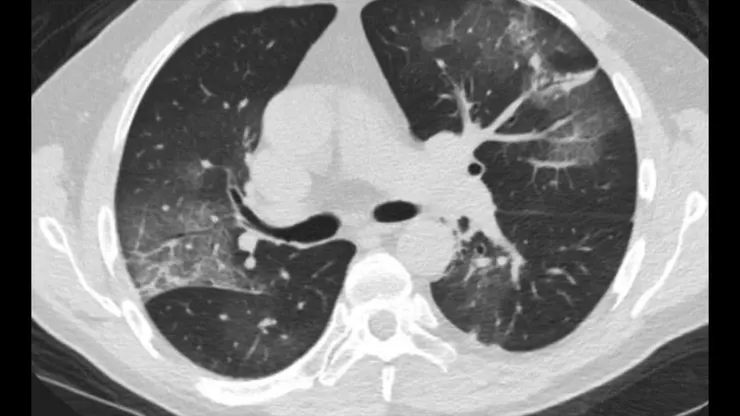

武漢研究

來自中國武漢的一項研究描述58位完全無症狀患者的CT掃描顯示 : 主要位於肺的外周(44%) 和肋膜下區域(75.9%),主要在一個 (38%) 或兩個肺葉(65.5%)。 肺部混濁是朦朧的白色雲層(CGO) 病變傾向於分佈在下葉(左62.1%, 右 68.9%)。而且58位完全無症狀患者,【94.8%】的CT掃描是有明顯病變。

研究人員觀察了鑽石公主號遊輪上乘客的CT掃描。在沒有咳嗽或發燒等症狀的76人中,有【54%】的人表現出明顯的肺部異常

特別是肺部浸潤。肺部浸潤似毛玻璃現象,形成了朦朧的白色薄雲層,與肺部的黑暗形成對比,這通常表明肺部充滿了發炎液體,來自細菌和免疫細胞戰爭後的成果。